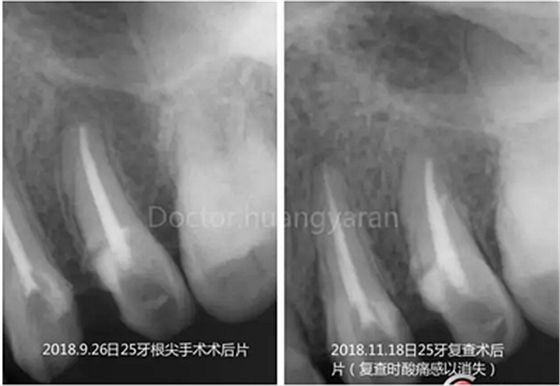

拍攝根尖片檢查,24、25牙根充到位,但考慮到可能是治療過(guò)程中消毒不到位導(dǎo)致,所以重新對(duì)25牙做根管治療,但酸痛感無(wú)減輕,于是考慮到根尖骨穿孔的可能性,與患者溝通后做診斷性翻瓣,翻瓣后發(fā)現(xiàn)根尖處無(wú)頰側(cè)骨板直接暴露,當(dāng)即行根尖切除術(shù),對(duì)位縫合,經(jīng)兩個(gè)月恢復(fù)根尖已無(wú)酸痛感!

根尖骨穿孔病歷常出現(xiàn)在有外傷史和正畸史或有錯(cuò)郃畸形的病歷中,受刺激后出現(xiàn)的術(shù)后反應(yīng)往往通過(guò)根管治療無(wú)法恢復(fù),只有通過(guò)根尖手術(shù)的方式可以解除